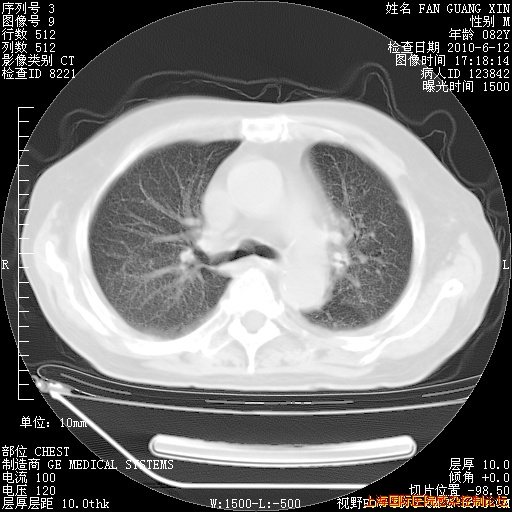

补发6月12日肺部CT肺窗

6月12日肺窗

整整相隔30天的肺部CT好像有所好转啊。甲强龙减量第3天,需要观察体温。

海管,自昨日你和我通完话后,不知您岳父消化道症状有无缓解?体温怎样?阅读7.12日胸部ct,个人认为目前激素治疗是有效的,甲强龙减量是适宜的。因在抗痨治疗,需密切观察肝功、肾功能和血常规。不过,老年、长期住院和大量使用激素,很担心菌群失调发生